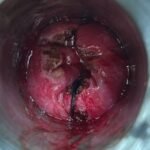

LASER LIAS FOR ANAL FISSURES AND BANDING OF HEMORRHOIDS